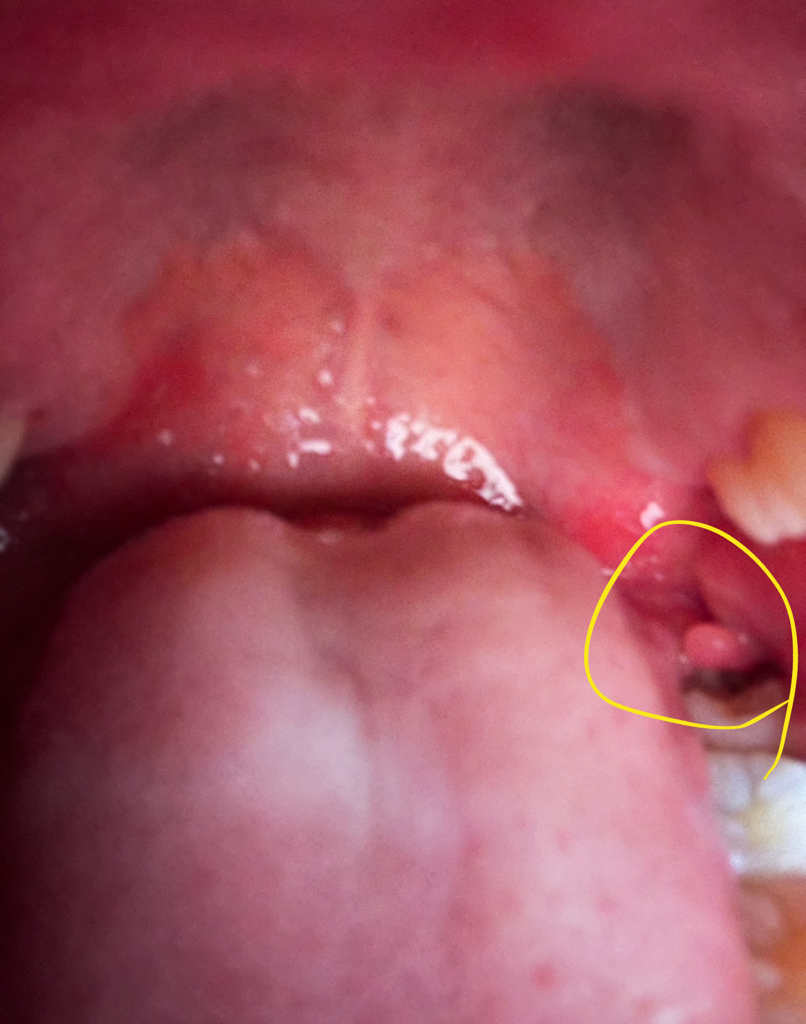

사랑니쪽 잇몸에 이상한게 났어요(사진주의)

사랑니 잇몸쪽에 언제부턴가 저런게 있더라구요,, 원래부터 있던건지 그건 모르겠는데 저부분 건드리면 많이 아파요ㅠ 저부분에서 악취도 나구요,, 저게뭐죠도대체... 이해하기쉽게 알려주시면 감사하겠습니다..

사랑니쪽에 잇몸이 과증식되서 저렇게 보이는거 같습니다. 저부위로 음식물이 들어가서 염증이 생긴거 같으니 치과에 가셔서 일단 잇몸치료를 먼저 받아보세요.

사랑니가 맹출하면서 잇몸이 사랑니 위에 얹혀 있다면 해당부위에 이물질이 들어가거나 해서 염증이 생기고 냄새가 날수 있습니다. 사랑니라 문제를 발생시키는 경우 발치를 해주는것이 좋을수 있습니다.

사랑니 주변 염증으로 인한 육아조직 증식입니다.

사랑니를 발치하실때가 되신것 같습니다.

사랑니가 발치되시면 병소의 근원이 사라지기 때문에 해당 병소도 사라집니다.

pericononitis로 인한 만성 자극으로 증식된 육아조직이 사랑니 상방을 덮고 있고 그 부위가 상악 치아와 계속 저작되면서

더욱 자극받아 더 증식하는 악순환에 빠진것입니다.

해당 부위를 깨끗이 양치하시고 치과에 가셔서 약도 타드시고 사랑니도 발치하시길 바랍니다.